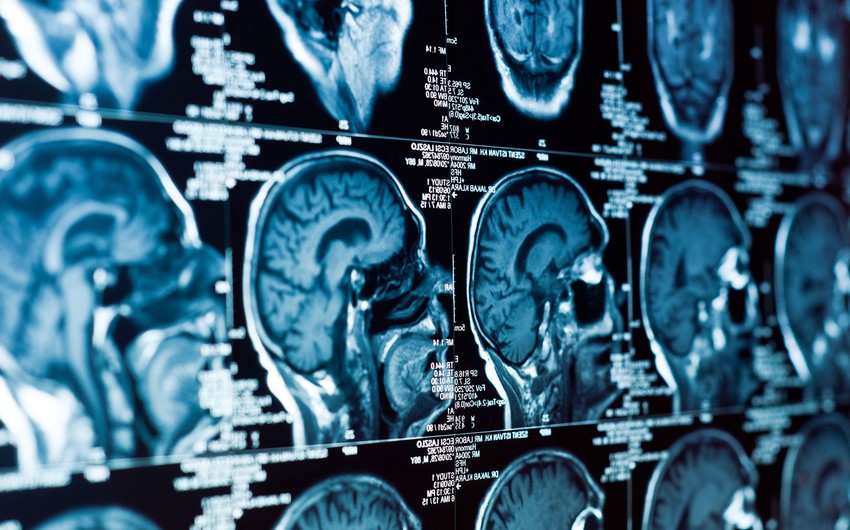

Standart üsullardan fərqli olaraq hüceyrələr birbaşa onurğa beyni mayesinə yeridilir ki, bu da müalicənin effektivliyini artırır. Sınaqlarda sağ qalma müddəti adətən 6-10 aydan çox olmayan təkrarlanan qlioblastoma (beyin şişi) olan 18 xəstə iştirak edib.

Testlər göstərib ki, xəstələrin 62%-nin şişləri ölçüsündə kiçilib və yeddi iştirakçıdan üçü (43%) bir ildən çox sağ qalıb. Bir xəstənin vəziyyəti isə artıq 16 aydır stabildir.